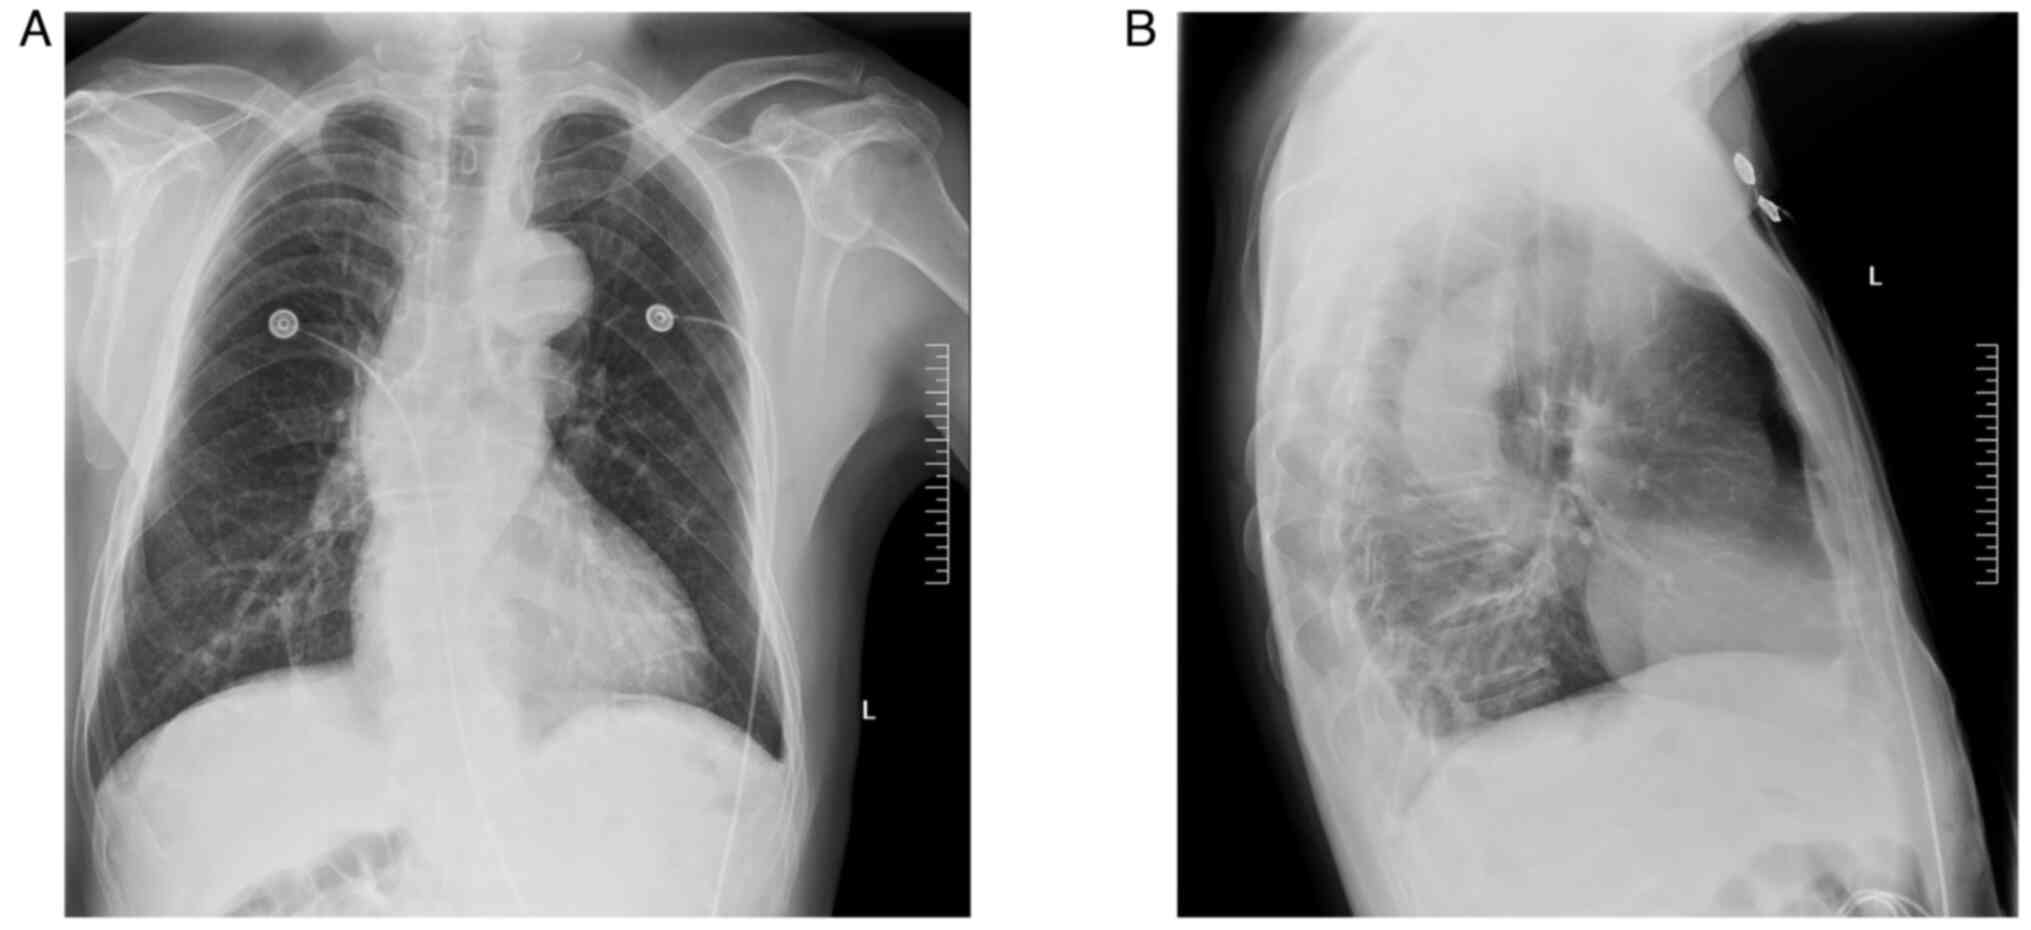

The case of a patient with type B3 thymomacomorbid with Chlamydia psittaci (C. psittaci) pneumonia exhibiting rare features is presented in the current report. The patient was admitted at the Second Affiliated Hospital of Jiaxing University (Jiaxing, China) with a history of direct contact with poultry. Clinical manifestations included fever, shivers, cough, fatigue and poor appetite. Chest computed tomography (CT) indicated right lung pneumonia, while metagenomics next‑generation sequencing using bronchoalveolar lavage fluid confirmed infection with C. psittaci. Additionally, positron emission tomography‑CT suggested the presence of thymoma. After surgery and treatment with doxycycline and imipenem cilastatin, the patient was discharged showing signs of improvement.

Figure 4

Figure 5